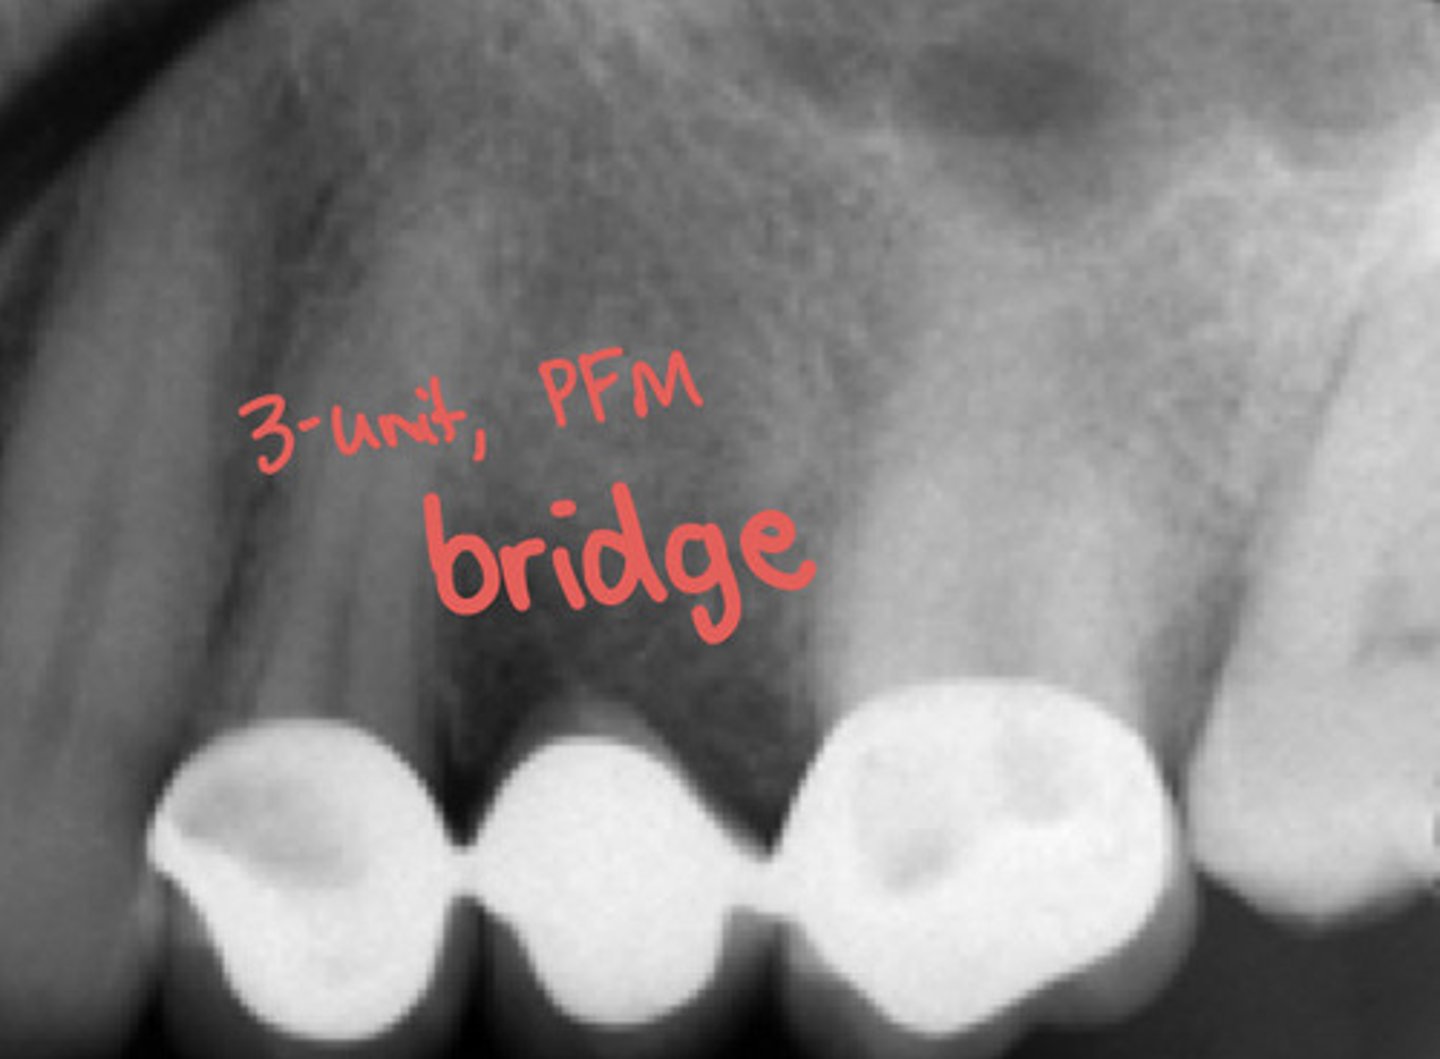

dental bridges

dental bridge radiographically?

porcelain fused to metal crowns